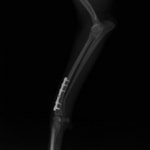

他院にて左大腿骨遠位の成長板骨折(salter-harrisⅠ型)が認められており、治療相談を目的として来院。当院にて、キルシュナーワイヤーを用いたピンニングにより骨折部位の整復を行いました。術後の経過は良好で、現在も経過観察中です。

術後レントゲン

機器

Arthrex社のターゲティングデバイスを用いてピンニングの位置を調整することで、確実な固定を行っています。当院ではこの手術器具以外にも、人の手術にも使用される様々な器具を導入し、手術精度を高め、また医療メーカーと新しい器具の開発、試作にも取り組んでおります。